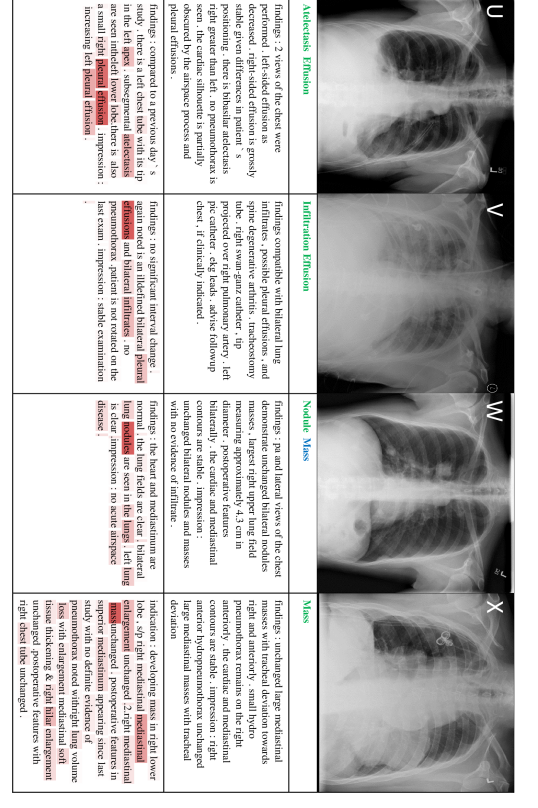

In this section, we present 20 more classification and reporting results (case E-X) from the proposed TieNet in addition to the four examples (case A-D) shown in the main paper. Sample images are illustrated along with associated classification Predictions (P), original and generated reports. Text attentions are highlighted with different saturation levels over the generated text. Darker red means higher weights of the text attention. Correct classification predications are marked in green, false predictions in red and missed predictions in blue.

Figure 9: 4 sample image Classification Predictions (P) along with original and generated reports. Text attentions are highlighted over the generated text. Correct predication is marked in green, false prediction in red and missing prediction in blue.

Figure 10: 4 sample image Classification Predictions (P) along with original and generated reports. Text attentions are highlighted over the generated text. Correct predication is marked in green, false prediction in red and missing prediction in blue.